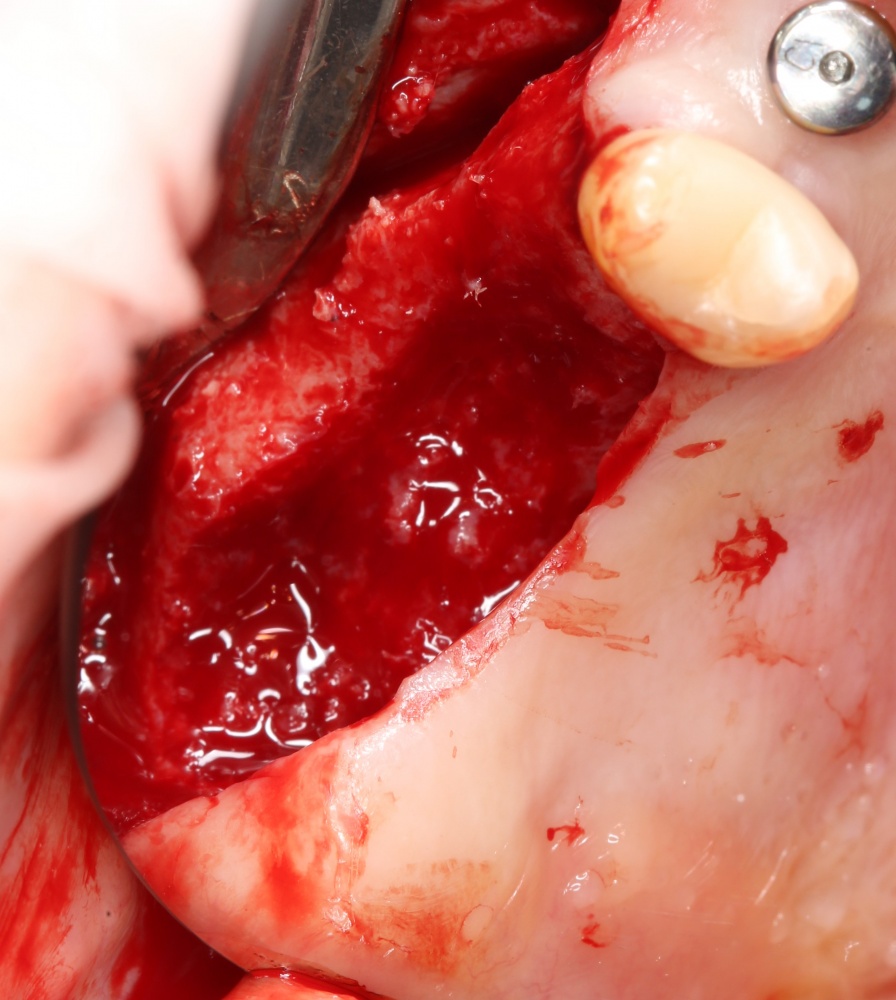

И, если в предыдущей части мы рассматривали ситуацию, когда принимающее ложе имеет относительно простой рельеф, и у нас не возникло сложностей с адаптацией аутоблока, то в случае, рассматриваемом сегодня, нормальная и точная адаптация крупного костного фрагмента, практически, невозможна. Именно поэтому мы решили использовать направленную костную регенерацию (НКР), поскольку с адаптацией тестообразного по консистенции графта проблем, обычно, никогда не бывает. Как, например, в этом случае:

То есть, выбирая метод остеопластики, мы, в первую очередь, рассматриваем не столько вопросы «применимости» и «результативности», ибо применить можно абсолютно все, сколько вопросы «удобства» и «упрощения» хирургических этапов. И, я повторюсь, в данном случае НКР просто проще.

В описываемом клиническом случае нам нужно замещать достаточно большой объем костной ткани, поэтому использование ксенографта (Geistlich Bio-Oss) выглядит совершенно разумным. Мы смешиваем его с аутокостной стружкой, источником клеток и факторов роста костной ткани, в пропорции, примерно 50/50, получая, при этом, около 3 куб см готового к использованию графта:

С помощью него мы «достраиваем» недостающую часть альвеолярного гребня, полностью перекрывая импланты. Напомню, что субкрестальные Ankylos Dentsply Implants вполне допускают такой подход.